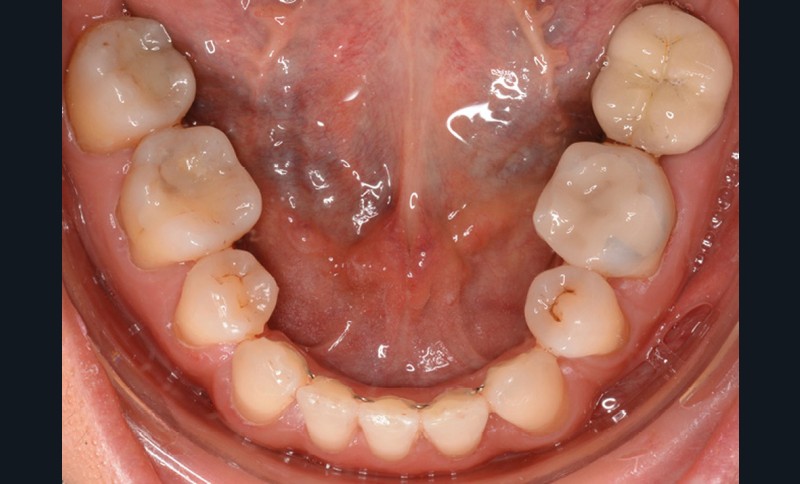

Présentation du cas (fig. 1 à 9)

Examen clinique

Sur le plan dentaire, la patiente est en classe III droite et gauche, canine et molaire de 6 mm, avec une occlusion inversée antérieure localisée à 11, 12 et 22. Elle présente une dysharmonie dents-arcades sévère, une agénésie d’une incisive mandibulaire est à signaler, et les troisièmes molaires ont été extraites à l’âge de 21 ans.